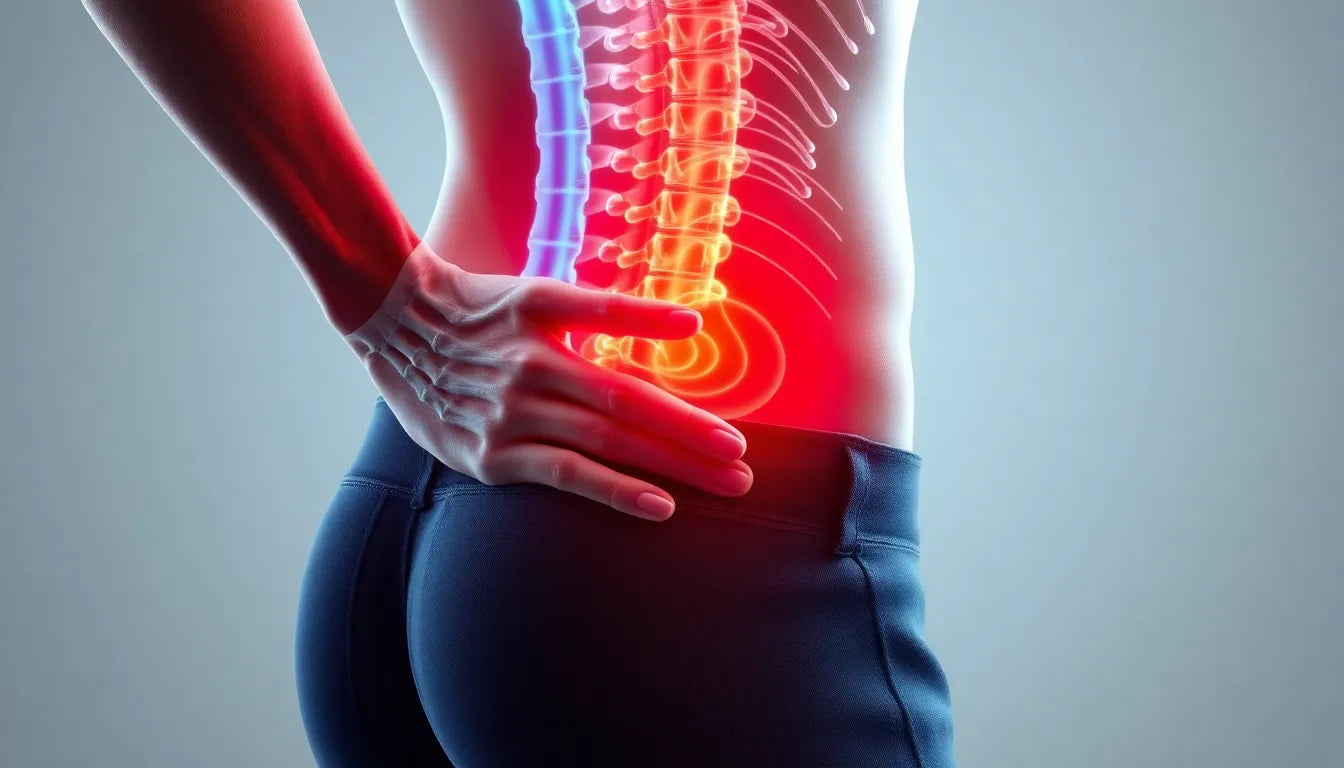

Rugpijn bestrijden: wat werkt echt zonder bijwerkingen?

Rugpijn is een veelvoorkomend probleem dat vaak met pijnstillers zoals paracetamol en ibuprofen wordt behandeld. Hoewel deze medicijnen verlichting kunnen bieden, is het belangrijk om hun effectivi...

Ontdek de verborgen oorzaken van pijn in de rechter onderrug en hoe je verlichting vindt

Pijn in de rechter onderrug is een veelvoorkomend probleem dat verschillende oorzaken kan hebben, zoals spierspanning, slechte houding, of zenuwproblemen zoals een hernia. Een holistische benaderin...